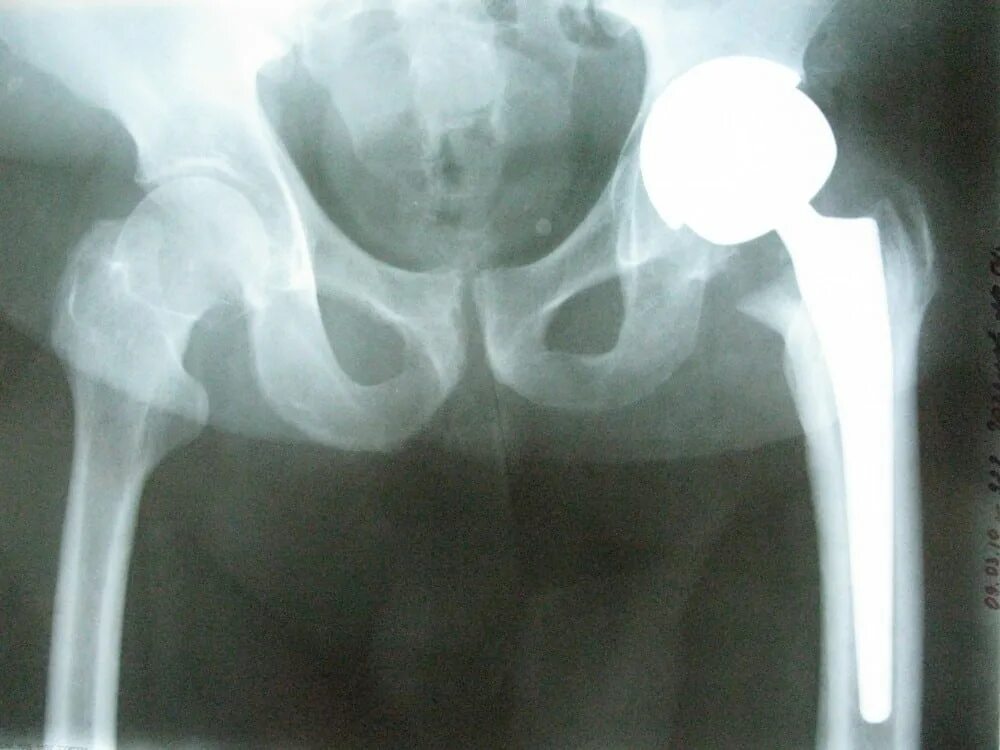

Анкилоз тазобедренного сустава